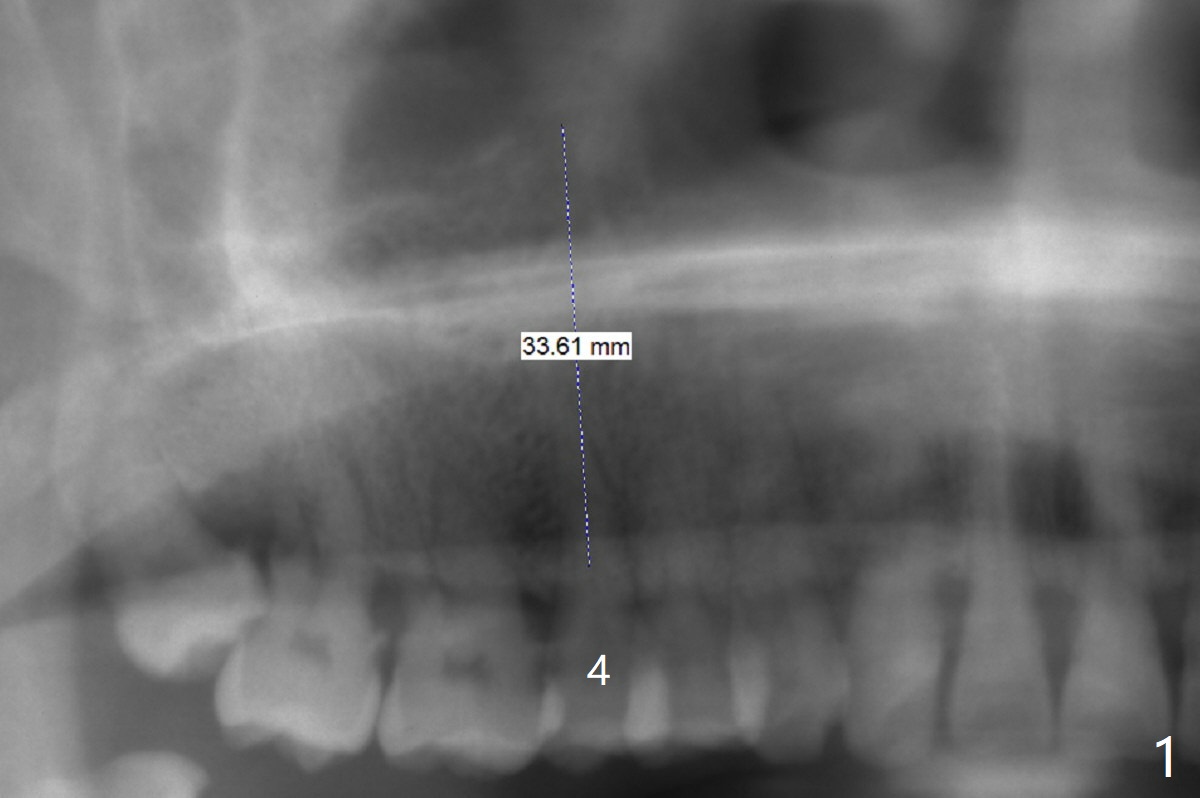

A 61-year-old man develops light pain associated with the tooth #4 with palatal subgingvial fracture (Fig.2 (*: periapical radiolucency)). Since the bone is apparent long (Fig.1), a long implant (15 mm bone level for guide, as long as 18 mm free hand or 20 mm tissue level) is to be placed for stability and early restoration. Because of palatal fracture in association with bone loss, the implant will be not placed too palatal. In fact the patient chooses to save the tooth with RCT.